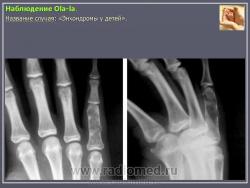

Энхондрома (син.: хондрома, центральная хондрома) — доброкачественная хрящевая опухоль, расположенная в костномозговом канале (интрамедуллярно). Встречается в 10 % случаев от общего числа доброкачественных опухолей костей. Считается, что она возникает из эктопически расположенных островков хряща, отщепившегося от пластинки роста на ранних этапах онтогенеза. В ряде случаев опухоль остается бессимптомной и обнаруживается случайно при рентгенологическом исследовании. В других случаях возникают боль и припухлость. Обычно болезненными становятся все энхондромы фаланг. Наиболее частая локализация: фаланги, главным образом, пальцев кистей, проксимальный конец плечевой кости, проксимальный или дистальный концы бедренной кости. При рентгенологическом исследовании в энхондроме определяются просветления с участками минерализации. Тень кости становится более широкой, кортикальный слой сохраняет целостность, но истончается. В редких случаях энхондрома имеет вид эксцентрически растущего экзофитного новообразования. Макроскопически опухоль представляет собой голубовато-белую полупрозрачную хрящевую ткань, в которую вкраплены желтоватые участки обызвествления. Опухоль состоит из отдельных хрящевых узелков, диаметр которых варьирует в пределах 1 см.

Энхондроматоз (син, болезнь Оллье) — редкая врожденная патология, не передающаяся по наследству, при которой у больных имеется множество доброкачественных хрящевых опухолей, главным образом на конечностях. Пораженная конечность укорачивается и деформируется. После завершения полового созревания заболевание не прогрессирует. Возможна малигнизация, которая отмечается в возрастном промежутке 13—69 лет. Локализация: энхондромы обнаруживаются в метафизах, диафизах, эпифизарных пластинках и суставных хрящах. Это интракортикальные и/или периостальные поражения в виде отдельных опухолей, не сливающихся друг с другом. Им присущ основной признак энхондроматоза — богатство клетками (гипериеллюлярность), причем встречается много двуядерных хондроцитов. И гиперцеллюлярность, и цитологическая атипия при энхондроматозе выражены значительнее, чем при солитарной энхондроме.

Рентгенологическая картина хондромы представляет четко очерченный опухолевый узел. Очаги минерализации в хондромах выглядят достаточно характерно и представлены очаговыми, глыбчатыми или кольцевидными , арочными отложениями извести. Полного разрушения кортикального слоя трубчатой кости с выходом опухолевых масс в мягкие ткани не наблюдается.